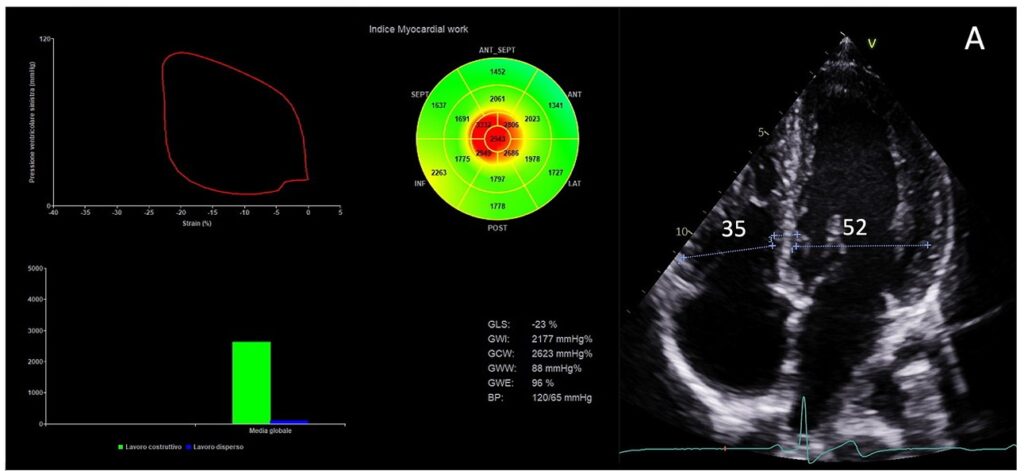

Não foram observadas diferenças em relação à fração de ejeção (FE), parâmetros de função diastólica e strain global longitudinal (SGL). Ainda, os parâmetros de trabalho miocárdico também foram similares entre aqueles com e sem HVE exc (GWI: p = 0.668; GCW: p = 0.862; GWW: p = 0.439; e GWE: p = 0.832).

Esses resultados demonstram, portanto, que atletas de endurance que apresentam remodelamento cardíaco continuam a apresentar parâmetros normais de trabalho miocárdico e sem diferenças significativas quando comparados com atletas que não apresentam remodelamento cardíaco induzido pela atividade física de alta intensidade.

Assim sendo, esses achados corroboram a natureza fisiológica das alterações estruturais encontradas nesta população, independente da magnitude do remodelamento. Vale destacar que aqueles que apresentam remodelamento, por sua vez, tendem a apresentar melhor performance nos testes funcionais.